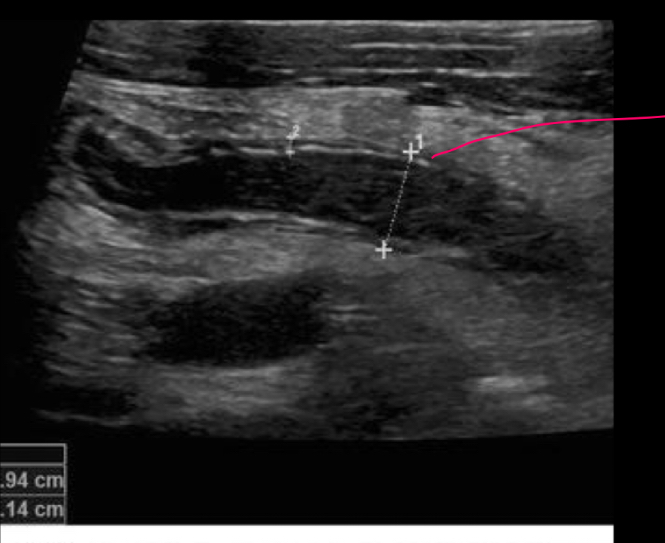

El us es util en quienes

niños en adutos es poco util

que es el dedo de guante

apendice distendida >7mm q se ve en US

Que signos se ven en US

dedo guante

Apendicolito

Liquido libre

Anillo de fuesgo: doppler

Que es

signo del guante

es casi imposible ver una apendice sana con US

verdad

US normal descarta patologia

NOO